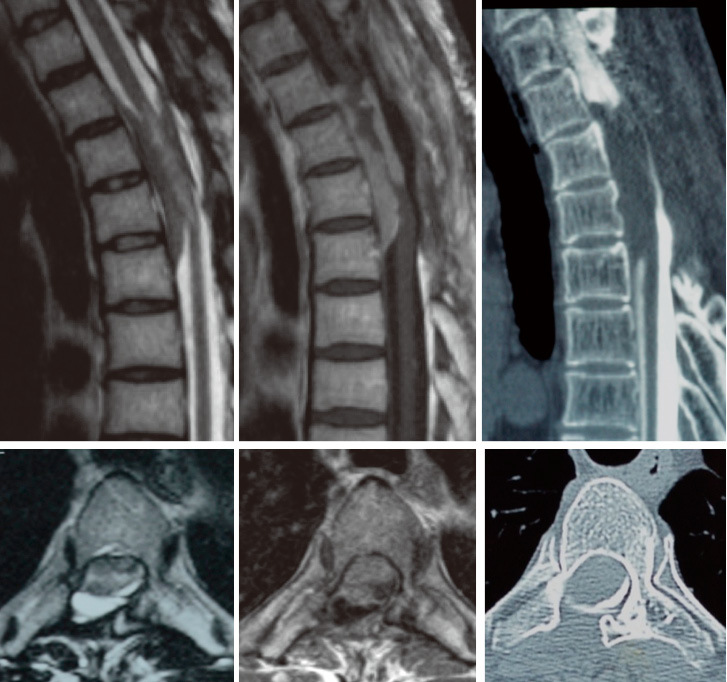

一名44歲男性,雙側下肢癱瘓,被診斷為胸椎硬膜內髓外腫瘤。進行了T2-4椎板切除術,同時切除了腫瘤并凝固了硬腦膜附件,組織學檢查顯示了一個不典型的腦膜瘤,分類為國際衛(wèi)生組織2級(圖1)。術后,下肢癱瘓完全緩解,但在46歲時,病情再次惡化。腫瘤切除進行了二次,但完全切除被放棄,因為在手術過程中運動誘發(fā)電位下降。48歲時,下肢再次無力。磁共振成像顯示脊髓周圍有一個T2-4硬膜內腫瘤,釓增強(圖2)。腫瘤附著在脊髓上,使得顯微鏡下難以區(qū)分脊髓和腫瘤。作為三次手術,進行了腫瘤次全切除、盡可能切除硬膜附件和T1-6后外側融合。腫瘤的組織學表現(xiàn)仍為不典型腦膜瘤(圖3)。54歲時,腫瘤增大,因此進行了立體定向放射治療,但無效。60歲時,患者出現(xiàn)胸痛,并被診斷為肋骨、腰椎和骶骨轉移瘤。此外,腦膜瘤直接侵犯并包圍胸椎(圖4)。除胸椎腦膜瘤外,全身CT掃描不能發(fā)現(xiàn)原發(fā)腫瘤。對肋骨轉移瘤進行了活檢,組織學發(fā)現(xiàn)顯示間變性腦膜瘤被分類為國際衛(wèi)生組織3級(圖4)。因此,患者被診斷為惡性轉化和椎管內腦膜瘤的遠處轉移。病人在61歲時去世。

圖2:T2加權,T1加權釓增強磁共振成像和計算機斷層掃描脊髓圖。硬膜內髓外腫瘤包圍脊髓,釓增強,無鈣化,無侵犯。